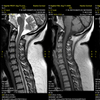

IRM Rachidienne

L’IRM rachidienne est un examen qui permet d’étudier l’ensemble du rachis et de la moelle épinière : rachis cervical, rachis dorsal, rachis lombaire.

L’IRM contribue à la détection des anomalies présentes au niveau des corps vertébraux et des disques.